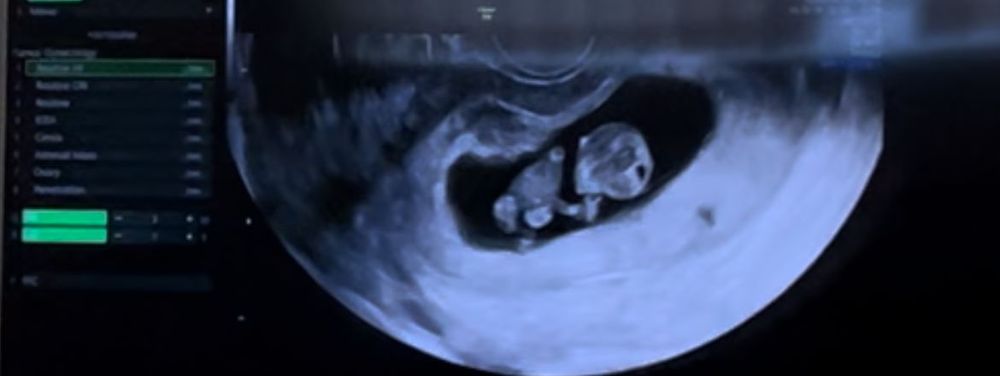

Дарина в Зачатие год Покидайте фото узи в 9 недель 🙏🏻 УЗИ Девочки у кого остались или есть фоточки покидайте пожалуйста! Хочу сходить в 9 неделек на узи, с монитором, хочется узнать как что там примерно видно будет Посмотрите еще 20 записей на эту тему Лучший ответ Елена 9н 2д двойня 02.11.2024 Ответить Отменить Ответить Таня Орозова 01.11.2024 Ответить Екатерина 01.11.2024 Ответить Екатерина Екатерина, чуть больше, 9,5 01.11.2024 Ответить Евгения 9+3 недели 01.11.2024 Ответить ЛисАлис 01.11.2024 Ответить Екатерина 01.11.2024 Ответить Екатерина Екатерина, 9 недель ровно, первое УЗИ 01.11.2024 Ответить Екатерина Екатерина, ножки попка к верху 😄 01.11.2024 Ответить Дарья 01.11.2024 Ответить Евгения Дарья , а вам делали трансвагинально или абдоминально? 01.11.2024 Ответить Дарья Евгения, трансвагинально . А вот 10 недель узи) 01.11.2024 Ответить Евгения Дарья , ух ты) а мне абдоминально делали😁 как в этот раз будут не знаю, пойду в другое место 01.11.2024 Ответить Евгения 01.11.2024 Ответить Мира В интернете нашла)) 01.11.2024 Ответить Девочки подскажите !! Пост нытья Чаты Беременных Выберите чат: Январята-2026 Февралята-2026 Мартята-2026 Апрелята-2026 Майчата-2026 Июнята-2026 Июлята-2026 Августята-2026